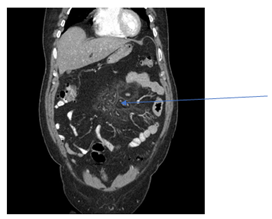

A 58-year-old white male with a past medical history of coronary artery disease, gastroesophageal reflux disease, hyperlipidemia and partially incarcerated umbilical hernia was referred to the surgeon by his primary care physician due to chronic right lower quadrant abdominal pain associated with one episode of non-bloody vomiting. He denied change in bowel habits, weight loss or blood in stools. On physical examination the only positive finding was that the abdomen was soft with mild tenderness in the right low quadrant and no peritoneal signs. Complete Blood Count (CBC), Basic Metabolic Panel (BMP) and Liver Function Tests (LFT) were essentially within normal limits. The total cholesterol was 316mg/dl, high density lipid was 38mg/dl and triglycerides level were 203mg/dl. Lactic acid, Erythrocyte Sedimentation Rate (ESR) and C-Reactive Protein (CRP) were also normal. CT abdomen/pelvis with contrast revealed increased mesenteric attenuation with induration and associated lymphadenopathy within the inferior midline abdomen (Figure 1). Lymph nodes demonstrated a halo of spared fat (Figure 2) consistent with sclerosing mesenteritis. The patient subsequently underwent elective laparoscopic epigastric and umbilical herniorrhaphy with mesh. The surgical specimen pathology consisted of adipose tissue. The histologic finding was mesothelial lined fibrous tissue showing chronic inflammation. It negative for malignancy including lymphoma. Upper Gastrointestinal Endoscopy (EGD) was performed and was negative for malignancy and Helicobacter Pylori. Patient was discharged from the hospital without any complications with pain medications. On subsequent follow up, the patient continued to complain of chronic mild right lower abdominal pain that was controlled with non-steroidal anti-inflammatory drugs . Repeat CT abdomen/pelvis one year later showed stable appearance of inflamed fat at the root of mesentery with numerous small lymph nodes (Figure 3).

Figure 2 Lymph nodes demonstrated a halo of spared fat.